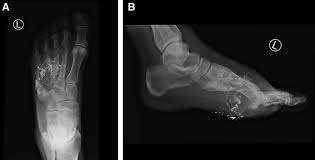

March fracture is also called ___ and looks like ?

stress fracture

gout

inflammatory arthritis commonly affecting the 1st metatarsophalangeal joint